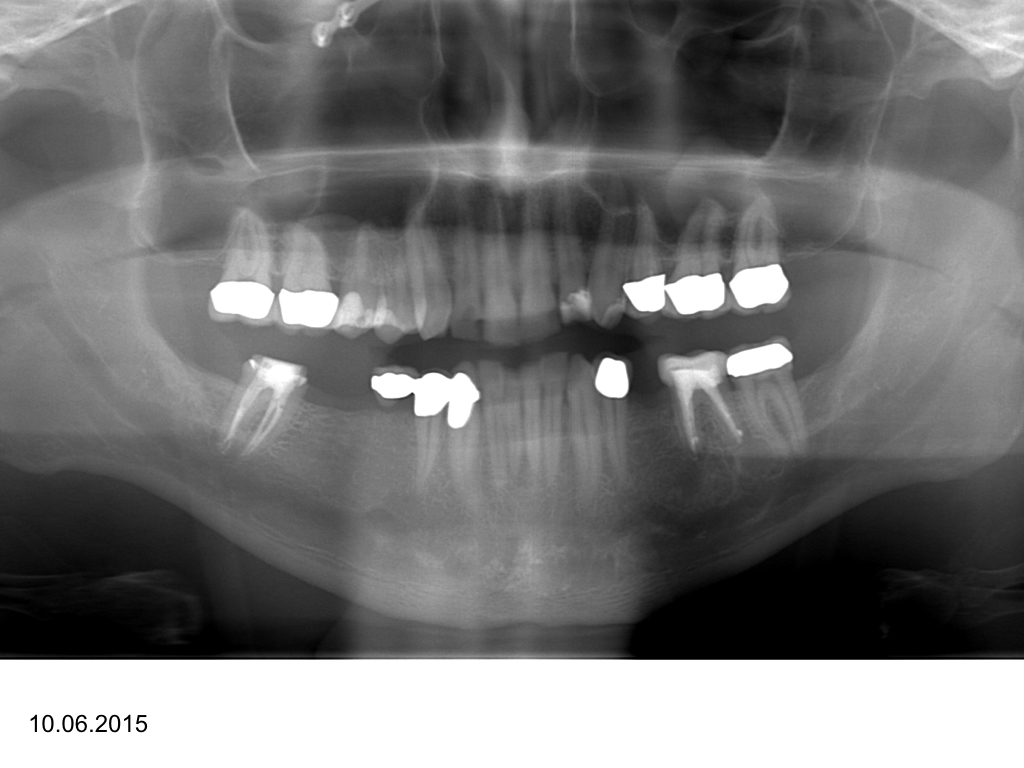

WS_Zy UK.005

Eine Fallvorstellung (2)